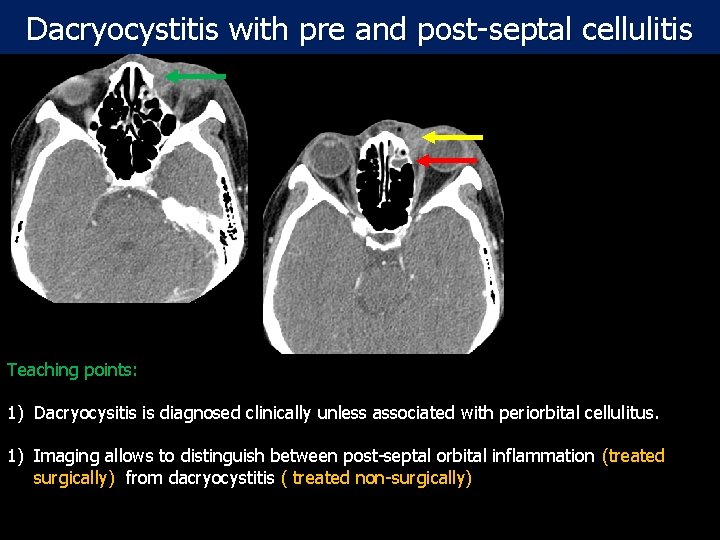

Dacryocystitis with pre and post-septal cellulitis Teaching points: Post- contrast CT scan: Axial and Coronal 1) Dacryocysitis is diagnosed clinically unless associated with periorbital cellulitus. images of the orbit in 47 year old female with left preseptal and post septal extra 1) Imaging allows to distinguish between post-septal orbital inflammation (treated conal cellulitis and dacryocystitis. surgically) from dacryocystitis ( treated non-surgically)